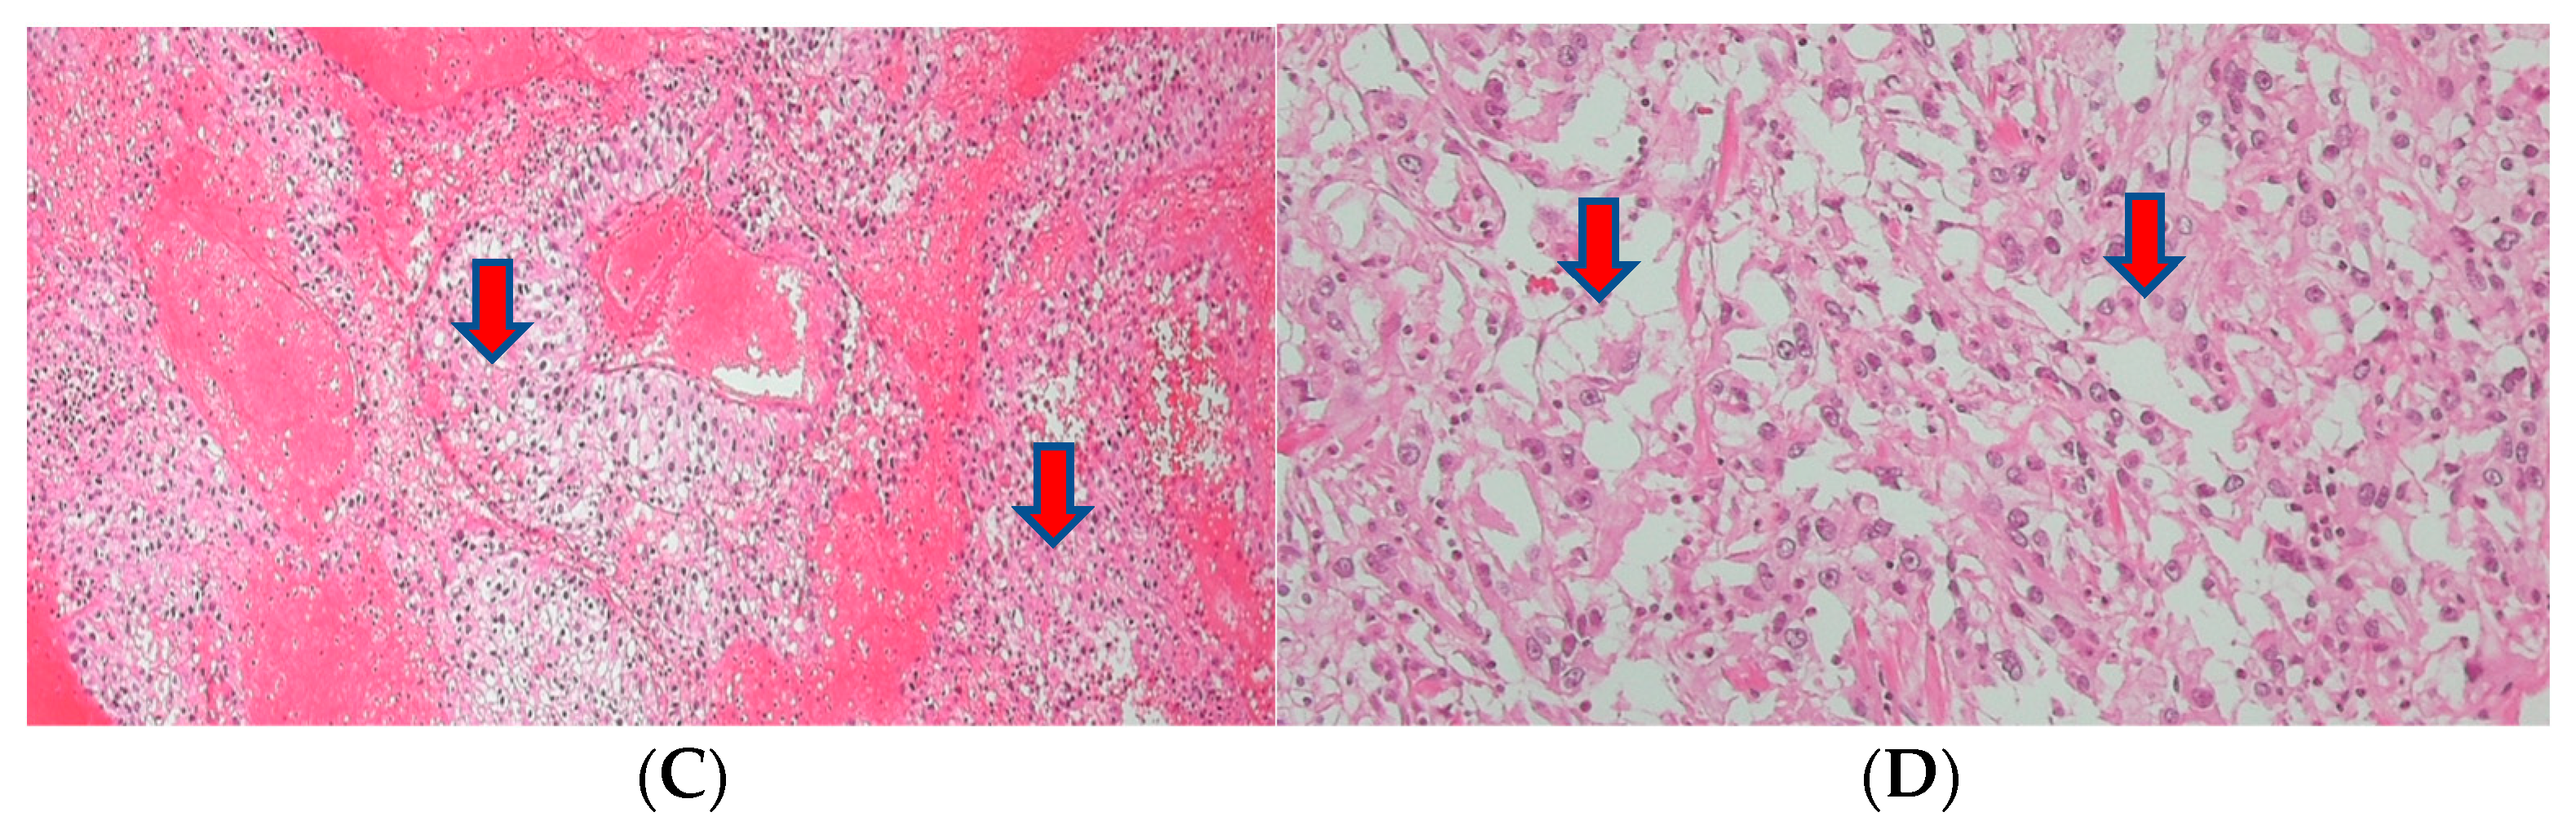

About a month after the surgical procedure, the patient began experiencing penile discomfort, which worsened over three months, prompting his hospital visit. Upon physical examination, a palpable mass was detected at the penoscrotal junction of the penis. The mass was tender, firm in consistency without ulcerations or rash, and measured approximately 5 cm in diameter. No other abnormalities were noted during the examination of the genitalia. Subsequent to this, a CT scan revealed an irregularly shaped enhancing mass in the penis, suggesting the possibility of metastasis (Figure 3). Laboratory results were within normal ranges. On urinalysis, pyuria was observed, but the urine culture showed no microorganism. Magnetic resonance imaging (MRI) findings revealed a lobulated contour and heterogeneously enhanced mass-like lesion in the corpus cavernosa of the penis on T2-weighted images, which raised the possibility of metastasis (Figure 3). A PET-CT showed an irregular increased fludeoxyglucose (FDG) uptake in the penis (Figure 3).

Figure 3.

(A) An irregularly shaped enhancing mass in the penis on CT scan. (B) Magnetic resonance imaging (MRI) findings showing a heterogeneously enhanced mass-like lesion in the corpus cavernosa of the penis on T2-weighted images. (C,D) PET-CT showing an irregular increased fludeoxyglucose (FDG) uptake in the penis.